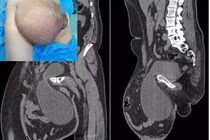

Thạc sĩ, bác sĩ Lê Thị Hoa, khoa Hồi sức Cấp cứu, Bệnh viện 09 – người trực tiếp điều trị cho anh Luân cho hay, năm 2003, khi cơ sở điều trị HIV còn hạn chế, bệnh nhân nhập viện trong tình trạng rất nguy kịch. Anh bị nấm, phổi, ho, sốt, cơ thể suy kiệt, gầy mòn, CD4 chỉ còn 19 tế bào/ml máu (ở mức 200, bệnh nhân đã được xếp vào giai đoạn cuối).